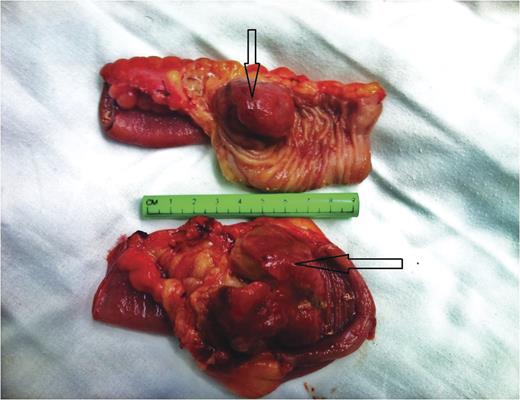

Under general anesthesia, patient in supine position, a midline laparotomy was performed. A large amount of abdominal fluid was aspirated and sent for culture and cytology. During running of the bowel at the level of 20 cm from the ligament of Treitz, an intussusception with a palpable intraluminal mass was found. Another intussusception 120 cm distal to the first was also noted (Fig. 2). No other pathologies were found. Double enterectomies with end-to-end anastamoses were performed. The patient was discharged home on Day 5 post op. Pathological analysis revealed polypoid and infiltrating intraluminal lymphoid proliferation (Fig. 3), extending to serosa and exhibiting diffuse aspect composed of medium-sized B-cells: pattern of Burkitt's Lymphoma. Abdominal fluid cytology analysis showed the presence of atypical lymphoid cells.

Intraoperative image of a double ileoileal intussusception. First one located ∼20 cm from the ligament of Treitz and the second about 120 cm distal to the first intussusception.

The surgical specimen comprised two segments of resected small bowel. Note the intraluminal mass (lead point) that caused the intussusception (arrows).